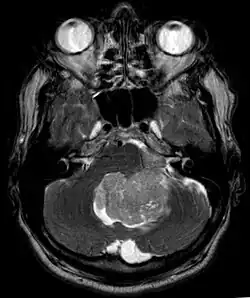

Ependymoma of 4.ventricle in MRI. -

An ependymoma is a tumor that arises from the ependyma, a tissue of the central nervous system. Usually, in pediatric cases the location is intracranial, while in adults it is spinal. The common location of intracranial ependymomas is the floor of the fourth ventricle. Rarely, ependymomas can occur in the pelvic cavity.

Ependymomas make up about 5% of adult intracranial gliomas and up to 10% of childhood tumors of the central nervous system (CNS). Their occurrence seems to peak at age 5 years and then again at age 35. They develop from cells that line both the hollow cavities of the brain and the central canal containing the spinal cord, but they usually arise from the floor of the fourth ventricle, situated in the lower back portion of the brain, where they may produce headache, nausea and vomiting by obstructing the flow of cerebrospinal fluid. This obstruction may also cause hydrocephalus. They may also arise in the spinal cord, conus medullaris and supratentorial locations.[7] Other symptoms can include (but are not limited to): loss of appetite, difficulty sleeping, temporary inability to distinguish colors, uncontrollable twitching, seeing vertical or horizontal lines when in bright light, and temporary memory loss. It should be remembered that these symptoms also are prevalent in many other illnesses not associated with ependymoma.